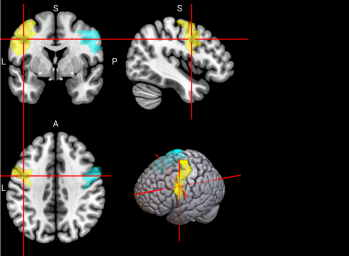

15,

16

L & R Supplementary motor area (SMA)

The SMA plays a role in self-initiated (voluntary) actions and is part of multiple voluntary motor loops [62].

/word/media/image11.png/word/media/image11.png